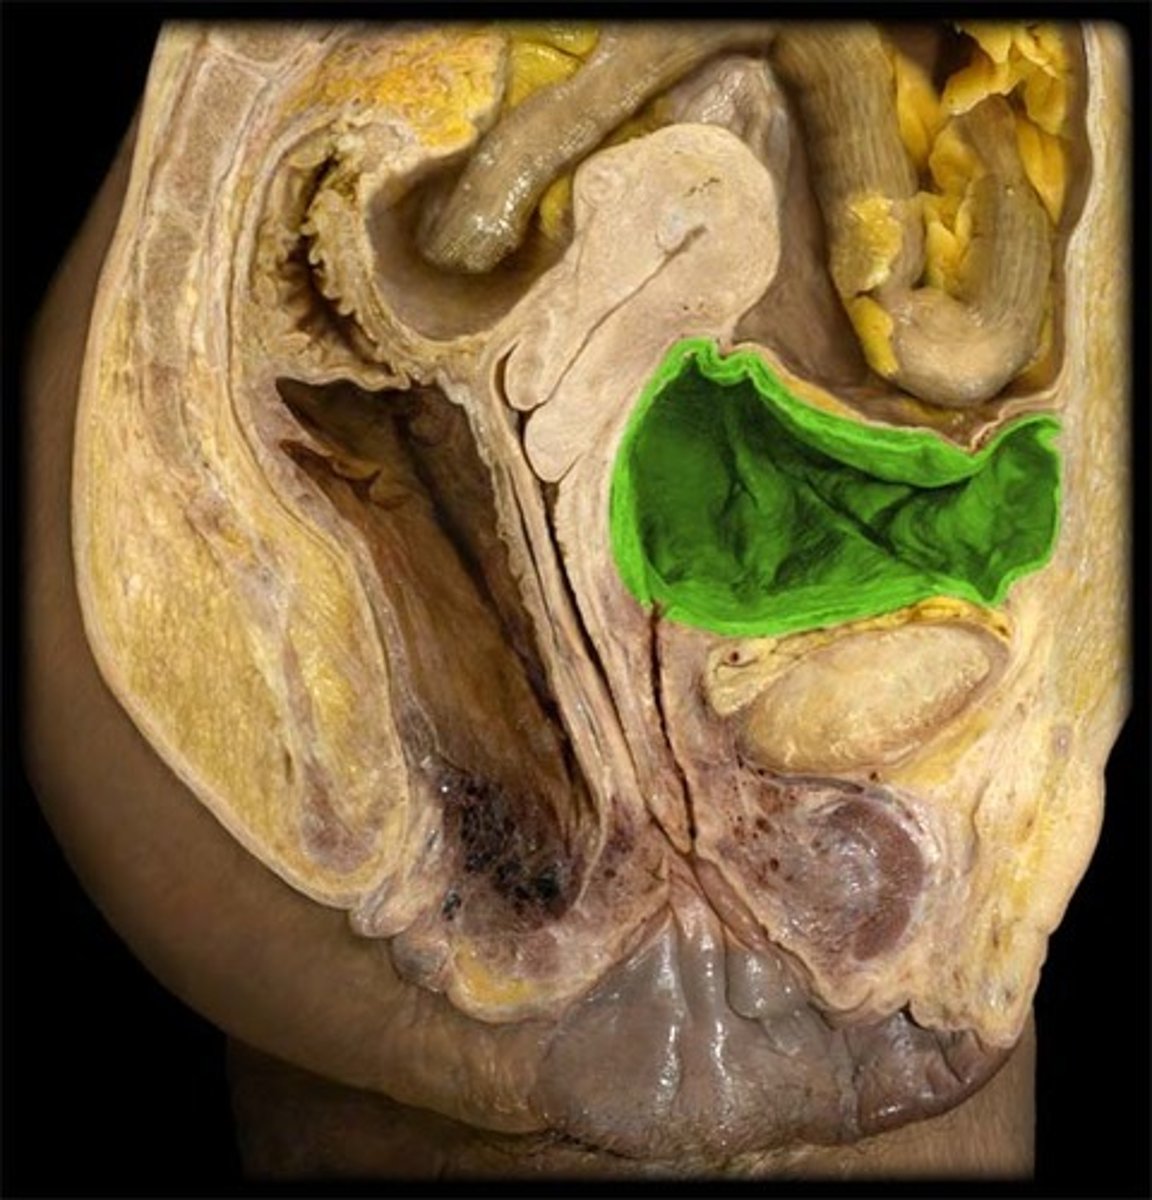

Urinary Bladder

Urinary Bladder

Broad Ligament